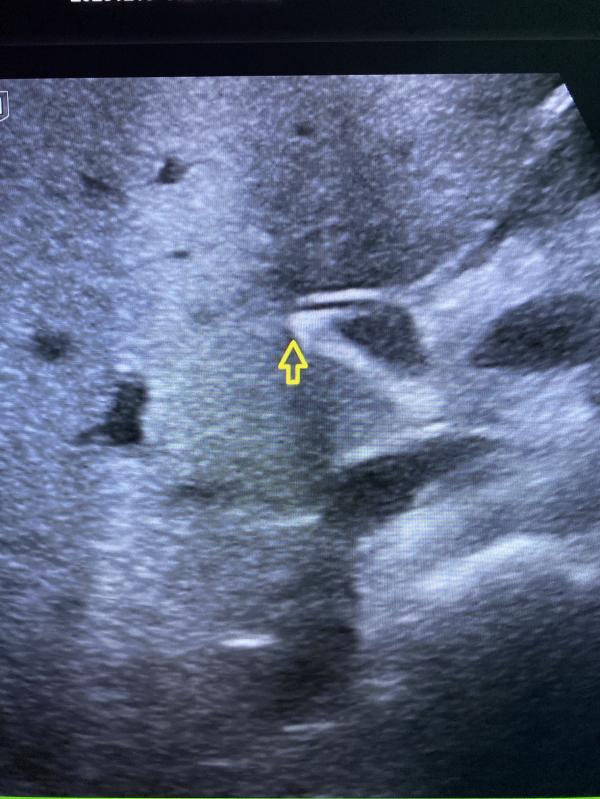

Камень в холедохе ( в общем жёлчном протоке).

Камень указан стрелкой.